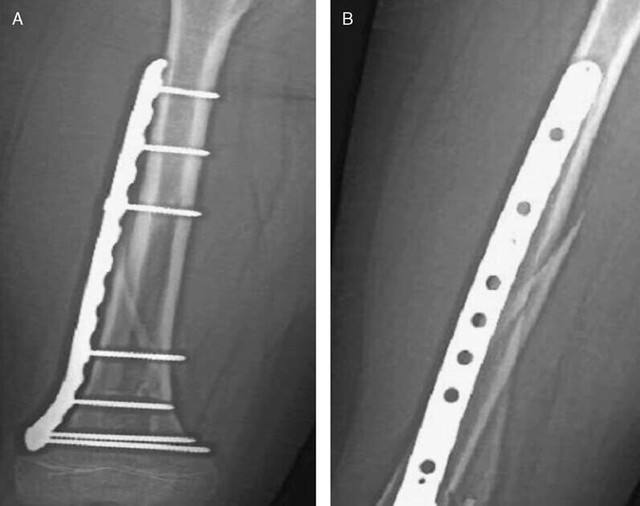

曙光骨科医师表示:骨折愈合后,钢板就可取出了。骨折愈合是指经过一段时间的内固定,原来骨折部位的连续性与稳定性。由骨组织生长而获得,从而使受伤肢体,能够承受各种生理应力。这个过程一般需半年至一年。>>>不知道自己现在能不能取钢板,点击在线咨询

钢板长期留置体内,可能与体液发生化学反应。骨折愈合后,取出内固定物。当然,对于高龄患者也可以不取出内固定物。>>>取钢板前需要拍X片吗?

钢板是否需要取出应在术前找医生咨询,务必要使骨头确实已经愈合的情况下方可取出,且手术应在正规医院内,由专业医生取出。江西省医学科学院附属嘉佑曙光骨科医院是江西省三级骨科医院,专注骨病骨伤,是洪城人民放心的骨科医院,多例案例被南昌主流媒体报道。